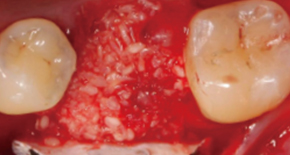

1. Extraction

2. Bone graft

3. SuturePain and swelling can be minimized and quick return to daily life is possible.